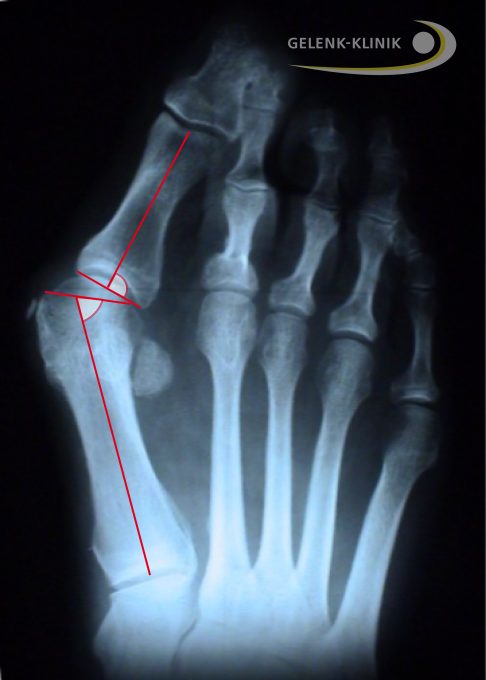

Ausschlaggebend für die gewählte Operationsmethode ist der Intermetatarsalwinkel, also der Winkel zwischen dem 1. und 2. Mittelfußstrahl. Die Operationen des Hallux valgus betreffen dabei verschiedene anatomische Bereiche des Fußes:

Bei einer milden Hallux valgus-Fehlstellung (< 17°) liegen noch keine wesentlichen Gelenkveränderungen (z. B. Arthrose im Großzehengelenk) vor. In diesem Fall eignet sich die Chevron-Osteotomie sehr gut.